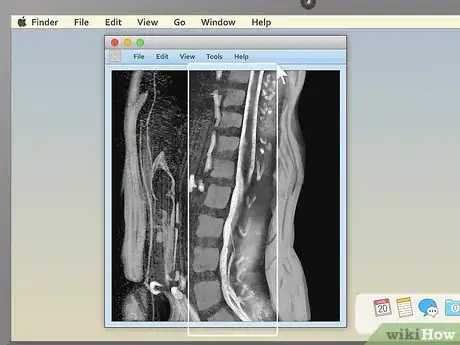

2. 2

Examine the structure of the vertebrae for spinal MRIs. MRIs of the spine are typically some of the easiest for non-doctors to read (especially in sagittal view). Look for noticeable misalignments in the vertebrae or fluid discs. Having just one of either be out of alignment (as in the example above) can be the source of serious pain.

• Behind the spinal vertebrae, in sagittal view, you'll see a white, rope-like structure. This is the spinal cord, the structure connected to all the body's nerves. Look for spots where the vertebrae or discs seem to "pinch" or press into the spinal cord — because the nerves are so sensitive, just a little pressure can lead to pain.